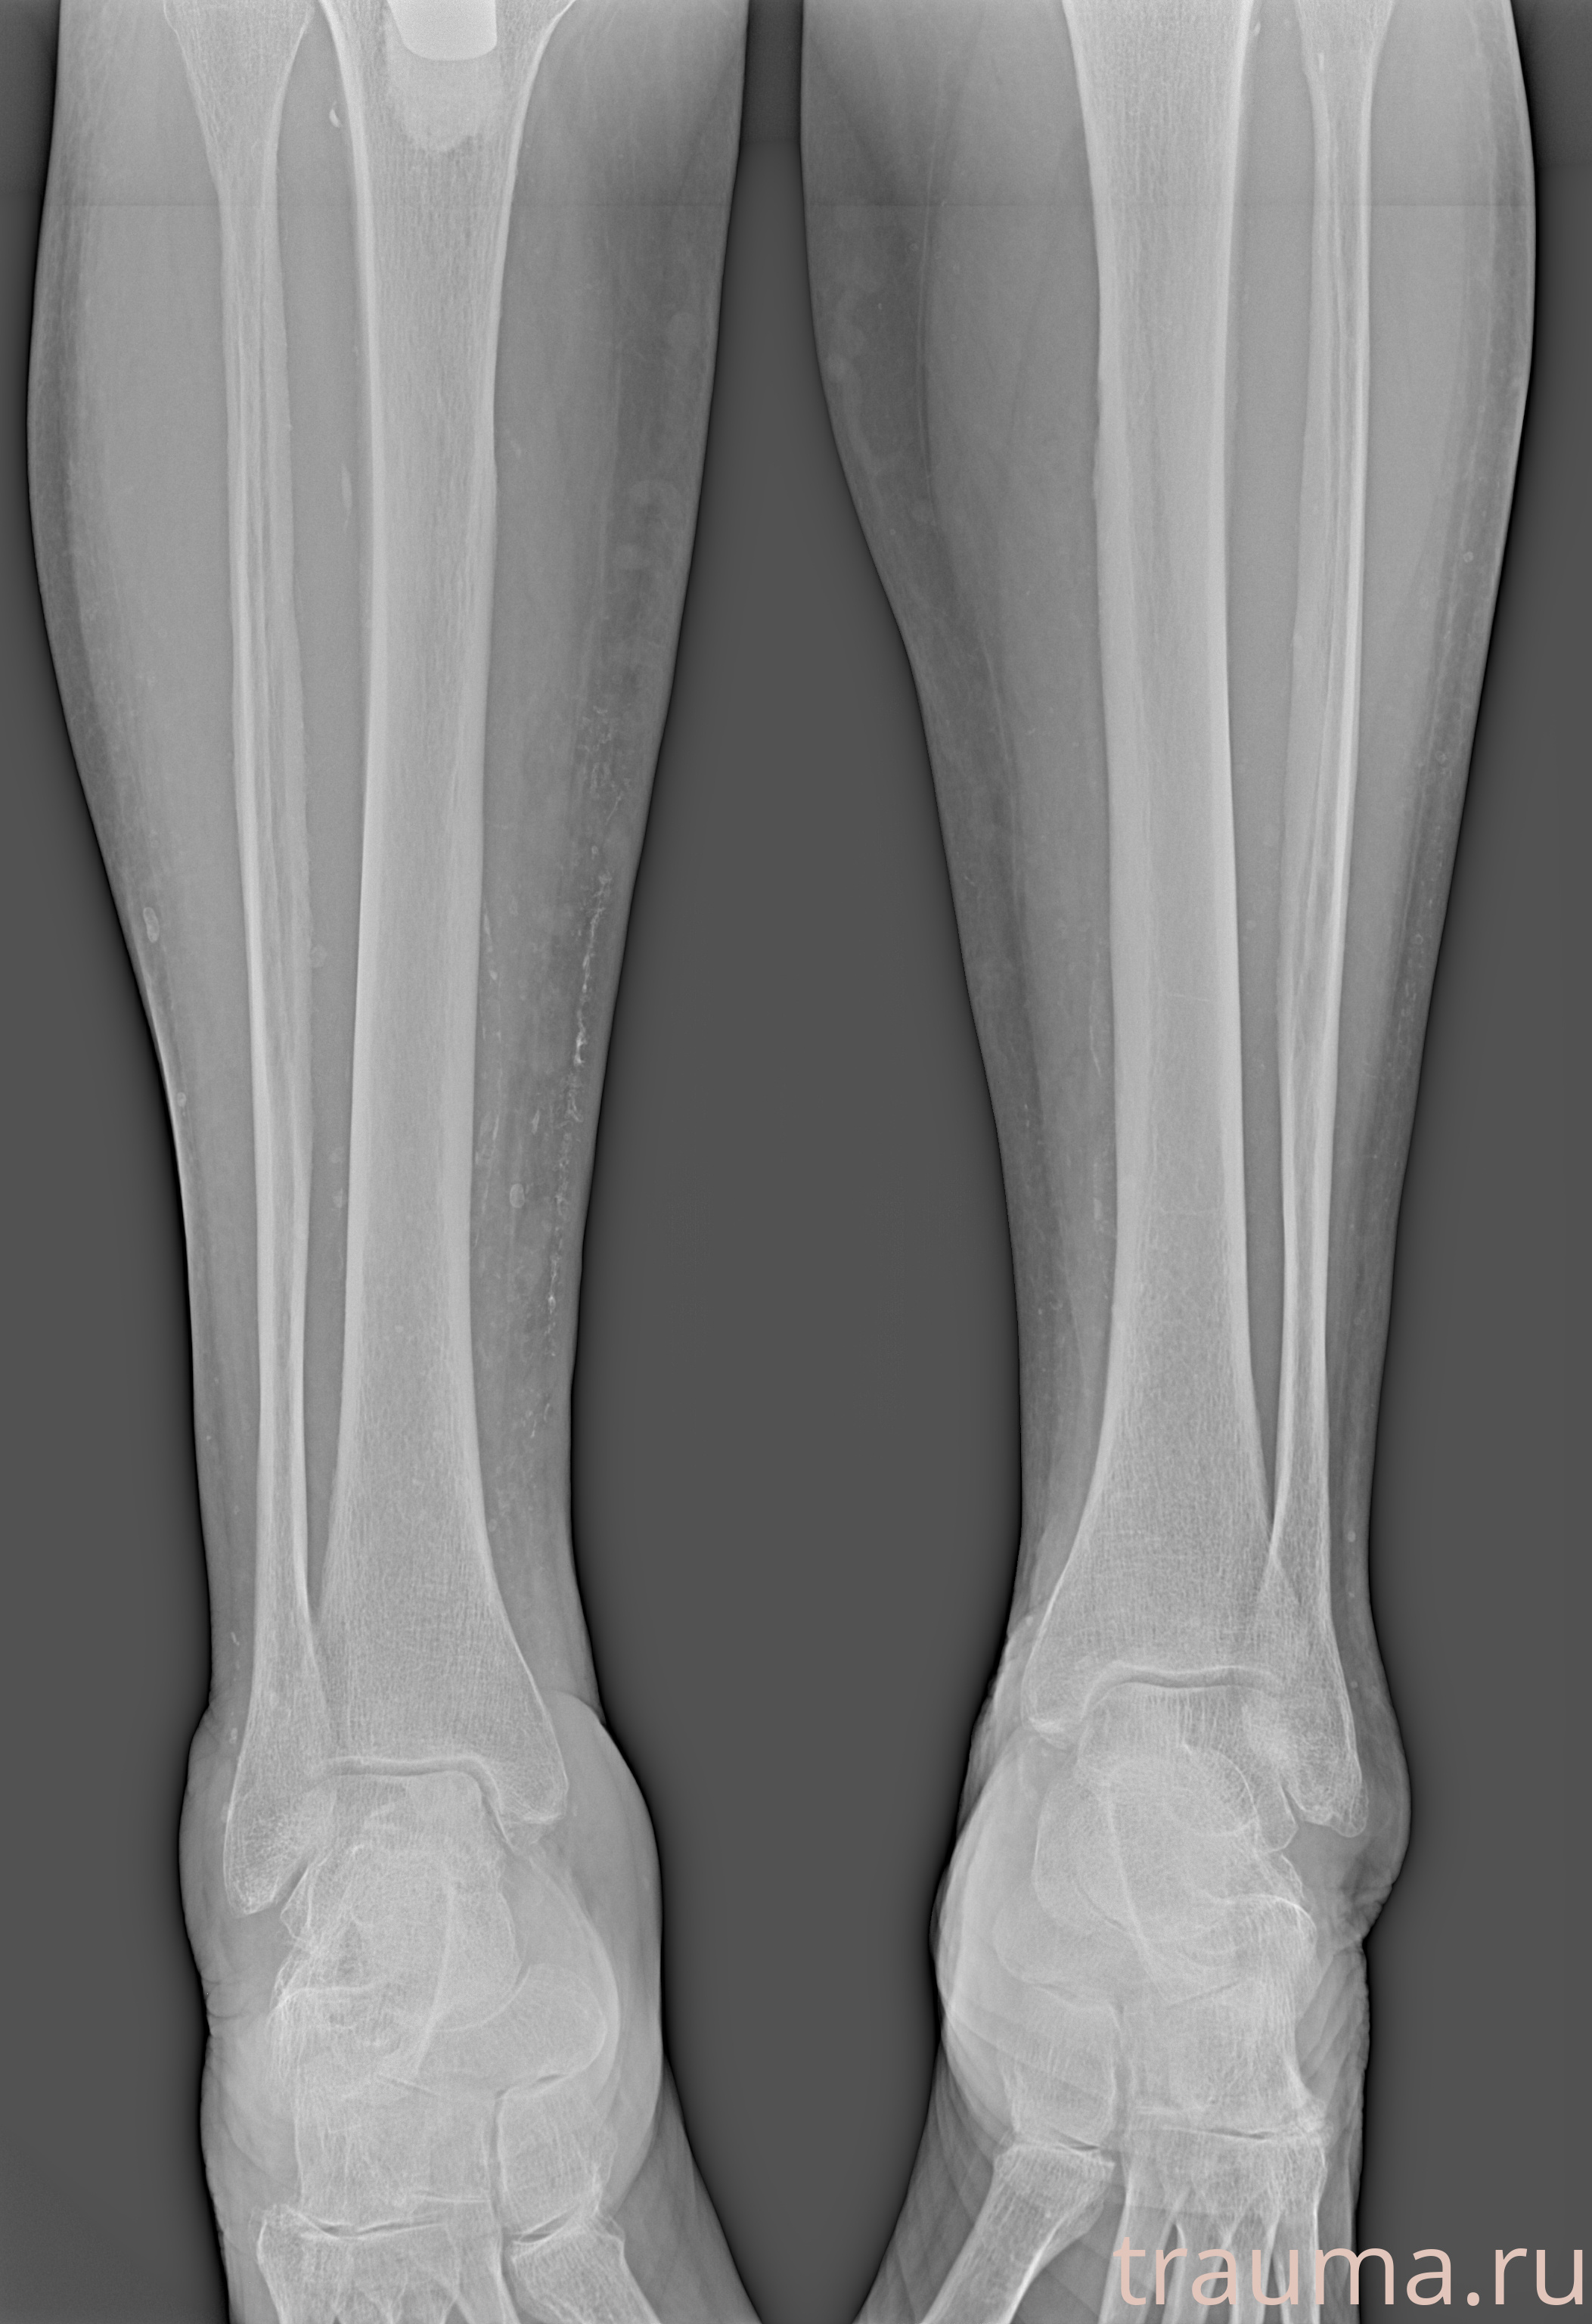

Рентгенограммы

Рентген на дому: по вашему адресу приезжает врач-рентгенолог, травматолог-ортопед с мобильным рентгеновским аппаратом, проводит диагностику травмы или заболевания, делает необходимые рентгенограммы, дает рекомендации по дальнейшему лечению. Получить качественные снимки в домашних условиях возможно благодаря уникальной методике, разработанной МосРентген Центром для института  Склифосовского